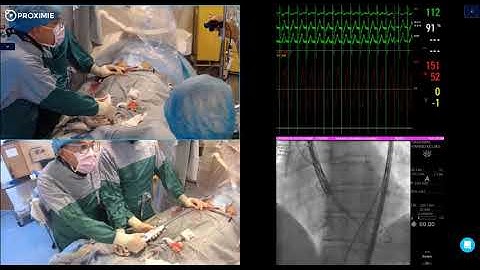

ABBOTT Portico Valve with FlexNav System Live in a Box